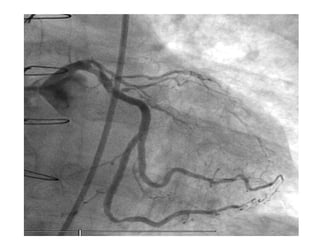

The document discusses several different cardiac conditions and test results including atrial fibrillation with complete heart block, second degree 2:1 heart block, complete heart block, atrial flutter with 2:1 block, amyloidosis indicated by an echocardiogram showing severe LVH, speckled appearance and low voltage limb leads on ECG, inferolateral reversible ischemia of moderate degree found on a graft study for a post-CABG patient which also showed an occluded superior OM and diseased OM2 and OM3 that were stented.